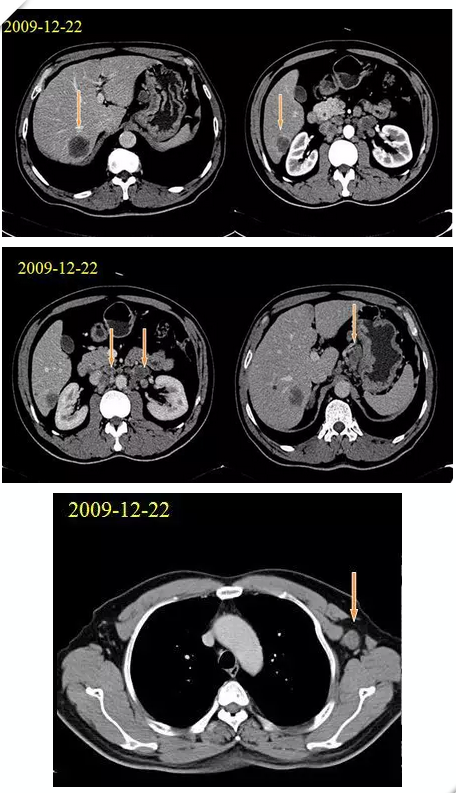

影像学检查

腹部CT平扫+增强(2009-12-22我院)示:肝脏多发转移瘤,腹膜后淋巴结转移。胸部CT(2009-12-21我院)示左腋窝淋巴结肿大,转移可能性大。

基线检查